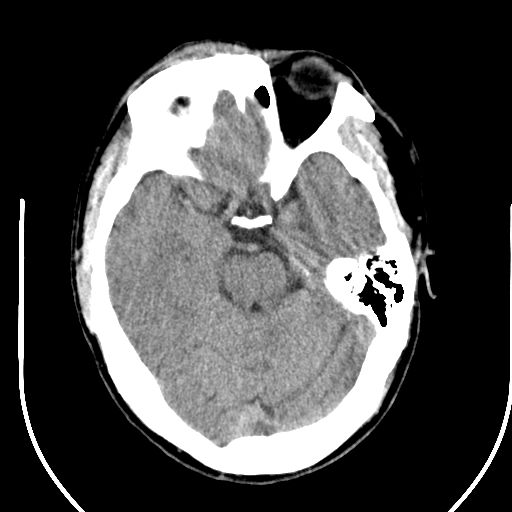

标题: CT25423:头部外伤意外发现右顶叶??? [打印本页]

标题: CT25423:头部外伤意外发现右顶叶???

ct值约13hu。

边缘清晰,没有占位效应,不像脑沟,结合ct值,软化灶可能吧

与脑沟没关系,小软化灶或陈旧性感染吧!

看样年纪不小了直接报腔梗,当然你要想报软化灶也是一样的

考虑右侧额叶巨腔隙灶;建议必要时行mri检查。